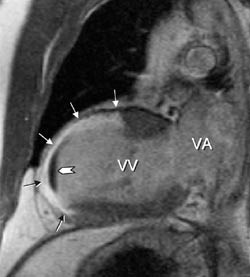

Den primære bildediagnostiske utredningen av kardiomyopati gjøres vanligvis med ekkokardiografi, men MR kan gi viktige bidrag ved flere typer av kardiomyopati. Fordi MR ofte gir en mer nøyaktig fremstilling av venstre og høyre ventrikkels veggtykkelse enn ekkokardiografi og en sikrere fremstilling av arrområder, kan metoden sannsynligvis sikrere skille mellom idiopatisk dilatert kardiomyopati og ventrikkeldilatasjon pga. iskemisk hjertesykdom. Ved hypertrofisk kardiomyopati kan MR vise den nøyaktige distribusjon av veggfortykkelsen og også avsløre og kvantitere en eventuell obstruksjon i utløpstractus av venstre ventrikkel (fig 3). Mitral insuffisiens, som ofte er til stede ved denne tilstanden, kan også påvises og kvantifiseres. Ved restriktiv kardiomyopati er en aktuell differensialdiagnose konstriktiv perikarditt. Ved sistnevnte sykdom kan MR påvise fortykket perikard.

Det er sjelden indikasjon for å gjøre MR-undersøkelse ene og alene for å evaluere klaffefeil, som regel kommer man til målet med ekkokardiografi. Når dette mislykkes, kan imidlertid MR være en god erstatning (15). MR-opptak som viser hjertets kontraksjoner og normalt sirkulerende blod med kraftig signal («hvitt blod») – såkalt cine-MR – vil vise høye blodstrømshastigheter og turbulens som bortfall av signal (fig 3). En klaffestenose ses derfor som en sort dusj (i det ellers hvite blodet) på medstrømssiden av klaffen, mens en insuffisient klaff ses som en sort dusj på motstrømssiden av klaffen (3, 4). Både stenoser og insuffisienser kan kvantifiseres.